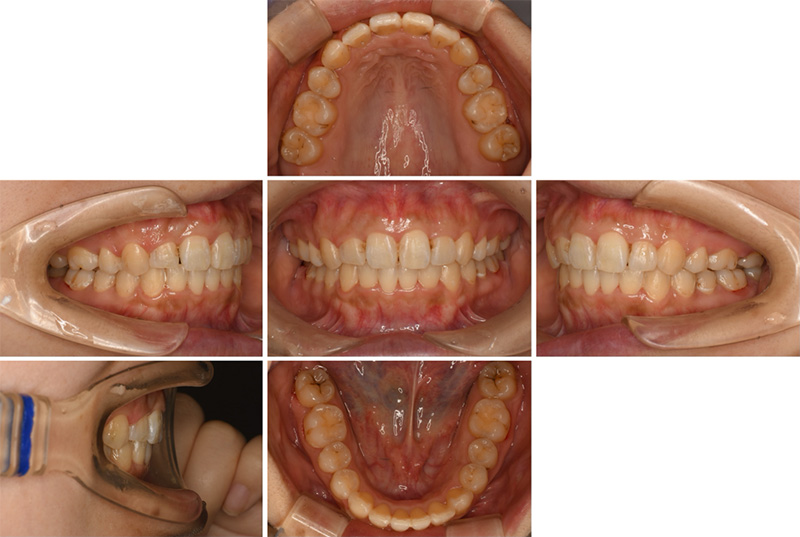

58歳女性

治療前

治療後

| 施術名 | インプラント治療 |

| 施術の説明 | インプラント治療とは、歯を抜いた所にチタン製の人工歯根を埋入し、新しく歯を入れる方法です。 |

| 施術の副作用 (リスク) | 腫れや疼痛を感じる、違和感を感じるなどの症状を生じることがあります。 |

| 施術の価格 | 53万円~+消費税 |